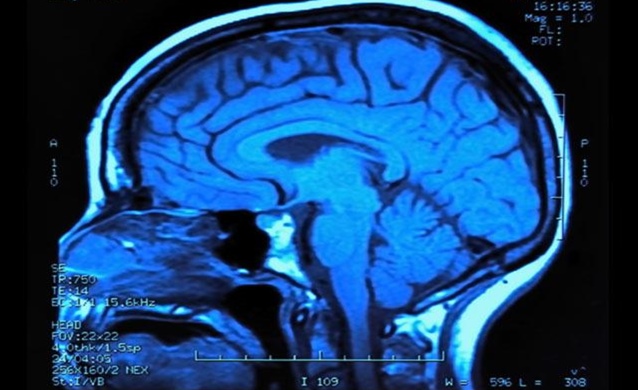

ปารีส 19 ก.ย.- ผลการศึกษาใหม่ชี้ว่า ประเทศร่ำรวยมีอัตราคนเป็นอัลไซเมอร์รายใหม่ชะลอลงจากที่ผ่านมา บ่งชี้ว่าการมีคุณภาพชีวิตที่ดีขึ้นอาจช่วยป้องกันการเป็นโรคสมองเสื่อมชนิดนี้ได้

วารสารเนเจอร์คอมมูนิเคชันฉบับเดือนเมษายนรายงานว่า ปีที่แล้วอังกฤษมีผู้ป่วยอัลไซเมอร์รายใหม่ 209,000 ราย ลดลงถึงร้อยละ 20 และต่ำกว่าที่คาดการณ์ในปี 2534 ว่าจะมี 251,000 รายจากแนวโน้มประชากรสูงวัยที่เพิ่มขึ้น บ่งชี้ว่าคนวัย 65 ปีขึ้นในอังกฤษมีแนวโน้มเป็นอัลไซเมอร์น้อยกว่าคนรุ่นก่อน แต่ยังไม่ทราบสาเหตุที่แน่ชัดว่าเกิดจากอะไร นักวิจัยบางคนคาดว่า อาจเป็นผลจากการมีสุขภาพหัวใจและหลอดเลือดหัวใจแข็งแรงขึ้น อันเกิดจากการตระหนักถึงอันตรายของการสูบบุหรี่ การเป็นโรคอ้วนและการไม่ออกกำลังกาย บางคนชี้ว่าอาจเป็นผลจากการรับประทานยาควบคุมความดันโลหิตสูงและคอเลสเตอรอล หรือการทำกิจกรรมกระตุ้นการทำงานของสมอง

องค์การอนามัยโลกเผยว่า ทั่วโลกมีผู้ป่วยสมองเสื่อม 47.5 ล้านคน เป็นผู้ป่วยใหม่ปีละ 7.7 ล้านคน สาเหตุของการเป็นโรคสมองเสื่อมมากที่สุดคืออัลไซเมอร์ คิดเป็นร้อยละ 60-70 ของผู้ป่วยสมองเสื่อมทั้งหมด อาการเริ่มจากการหลงลืมไปจนถึงสูญเสียความจำและต้องมีคนดูแลตลอดเวลาเพราะไม่รู้ทั้งเรื่องเวลาและสถานที่ ท้ายที่สุดผู้ป่วยอัลไซเมอร์อาจถึงขั้นไม่รู้วิธีรับประทานอาหาร วงการแพทย์รู้จักโรคนี้มานานกว่าร้อยปีแล้ว แต่ยังไม่สามารถหาวิธีรักษาและสาเหตุที่แน่ชัด เชื่อกันว่าสาเหตุหนึ่งเกิดจากแผ่นคราบโปรตีนสะสมในสมอง ขณะที่ผลการศึกษาเมื่อไม่นานมานี้โยงว่าอาจเกิดจากมลภาวะทางอากาศ เชื้อรา หรืออุบัติเหตุระหว่างการรักษา.- สำนักข่าวไทย